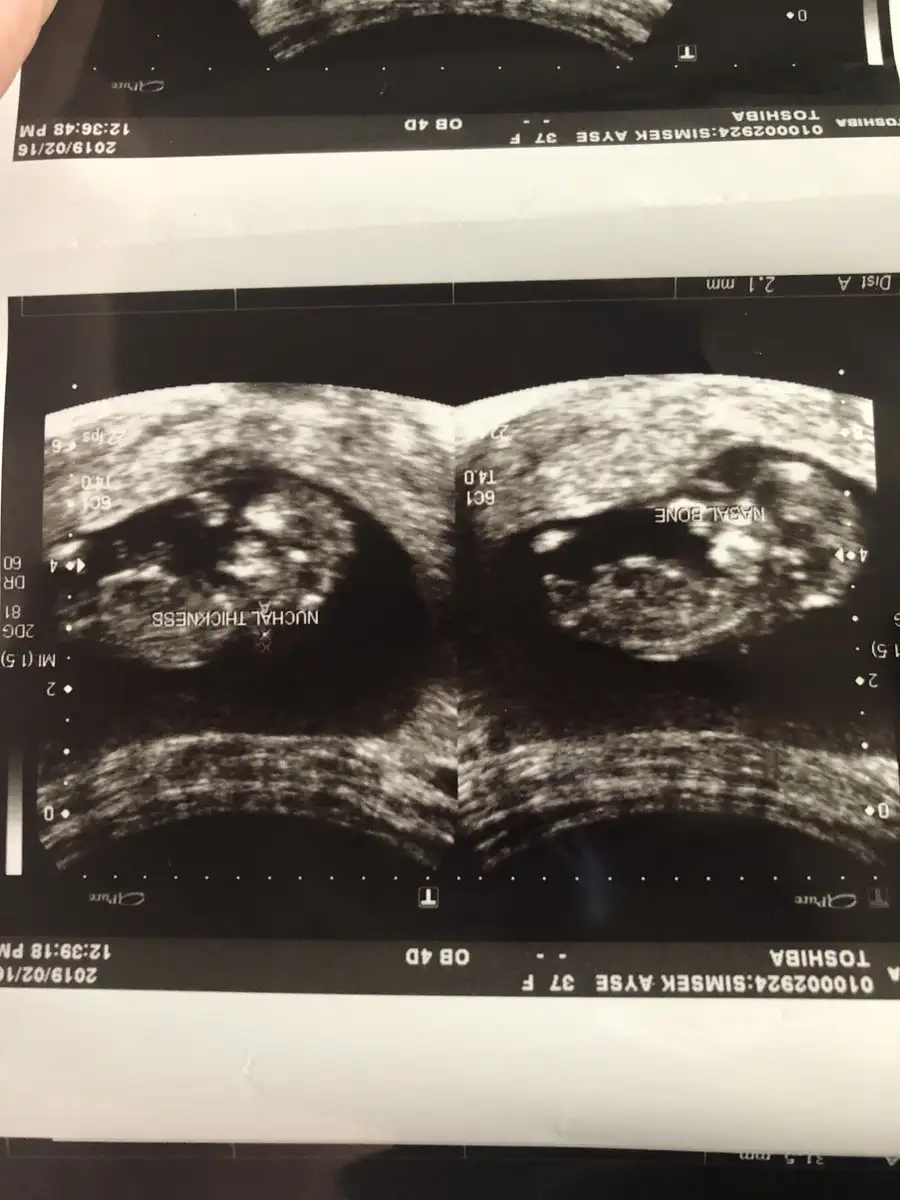

Ohh maşallah harika benim de hep ilerde gidiyo doktorum şimdilik bişey demedi bende sorun yoktur diye düşünüyorum herşeye endişelenir oldum@SLVESTER Merhaba! Canım ilk usg benden gelsin yorum alabilirmiyim. Bugün kontrol vardı ense burun vs. Herşey yolunda ama cinsiyet için erken dedi dr. Bide tam 12 haftalık çıktı normalde 11+3 olması gerekiyordu

Tşkler canım. Sağlıklı olsunlarda gerisi önemli değil şimdi de tarih değişti ağustos annesi oldum bende çok endişeli biriyim zor geldi bu ikincisi ama bugün gerçekten rahatladım onu böyle görünce çok güzeldi sağlıkla kucaklıyalım inşallahOhh maşallah harika benim de hep ilerde gidiyo doktorum şimdilik bişey demedi bende sorun yoktur diye düşünüyorum herşeye endişelenir oldum

Tşkler canım. Sağlıklı olsunlarda gerisi önemli değil şimdi de tarih değişti ağustos annesi oldum bende çok endişeli biriyim zor geldi bu ikincisi ama bugün gerçekten rahatladım onu böyle görünce çok güzeldi sağlıkla kucaklıyalım inşallah